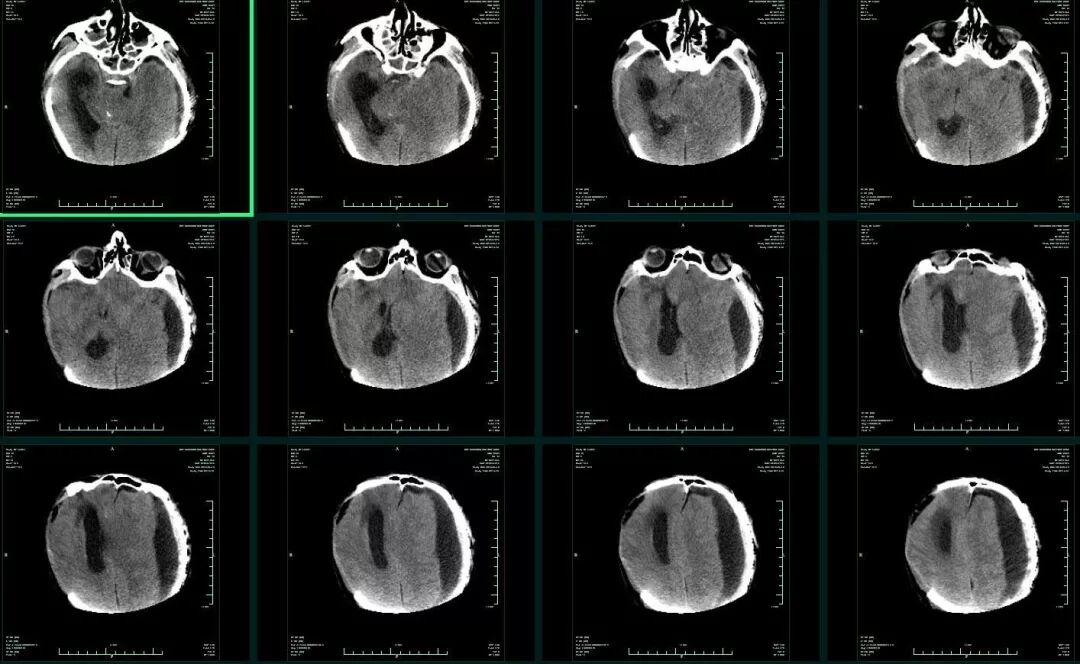

入院时患者深昏迷,GCS6分,左侧瞳孔0.5cm,右侧瞳孔0.3cm,对光反射均消失。急诊头颅CT提示:“左侧额颞顶部急性硬膜外血肿,脑疝(图1)”,急诊行左侧颅内血肿清除+去骨瓣减压术,术后即刻头颅CT复查提示:“右侧额颞叶急性硬膜下血肿”(图2),再次开颅行右侧颅内血肿清除+去骨瓣减压术。术后转ICU科呼吸支持治疗。术后再次复查CT,见血肿已清除,无硬膜下积液,中线基本居中(图3)。术后5天患者病情好转,GCS8分,双侧瞳孔0.3cm,对光反射迟钝,转回神经外科监护病房。

图2. 左侧急性硬膜外血肿清除+去骨瓣减压术后,出现右侧急性硬膜下血肿。